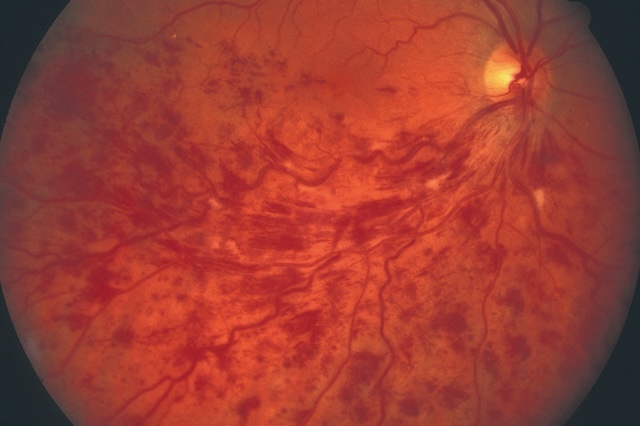

- • 2627les hémorragies intrarétiniennes :

- – hémorragies en flammèches (elles siègent dans le plan des fibres optiques, fig. 1.43),

Fig. 1.43 Hémorragies en flammèches. Photographie du fond d'œil révélant plusieurs hémorragies en flammèches disposées le long des fibres nerveuses rétiniennes. Les traînées rouges allongées sont bien visibles, orientées selon la disposition radiaire autour de la papille optique, située en haut à droite de l’image. Les vaisseaux rétiniens paraissent dilatés et irréguliers, avec une trame vasculaire dense marquée par des foyers sombres d’hémorragies plus profondes. L’ensemble traduit une atteinte marquée de la rétine au niveau vasculaire, sans obstruction apparente du nerf optique.

- – hémorragies profondes, volumineuses, « en taches » (fig. 1.44).

Fig. 1.44 Volumineuses hémorragies profondes, en taches (+ nodules cotonneux). Cette photographie couleur du fond d’œil révèle une atteinte rétinienne sévère caractérisée par la présence de volumineuses hémorragies profondes disposées en taches irrégulières, particulièrement concentrées dans la région temporale supérieure. Ces hémorragies, d’un rouge foncé dense, coexistent avec des nodules cotonneux blanchâtres, situés dans les couches superficielles de la rétine. La papille optique reste visible en temporal interne, de teinte jaune pâle, avec un réseau vasculaire rétinien montrant des trajets légèrement déformés, probablement en lien avec l’œdème adjacent. L’aspect diffus et étendu des lésions suggère un processus ischémique ou inflammatoire marqué, fréquemment rencontré dans des contextes de rétinopathie hypertensive, diabétique ou infectieuse avancée. L’hétérogénéité des couleurs et la disposition anarchique des saignements et exsudats renforcent l’aspect pathologique avancé visible sur cette imagerie rétinienne.